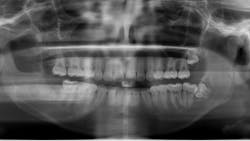

At the time of publication, the lesion described had reduced in size dramatically, now extending from tooth nos. 10–12. The floor of the maxillary sinus ossified as well. The time elapsed since the marsupialization procedure was six months. Removal of the residual cyst with immediate bone grafting would be performed shortly, likely including the sacrifice of the lateral incisor and second bicuspid. Although this is a large defect, it will be much more easily managed than that posed if marsupialization had not been utilized (figure 7).